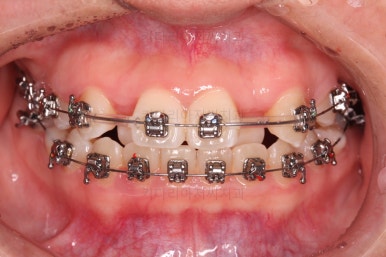

미니스크류가 등장했네요.

아랫니는 아무 생각 없이 당기기 해주면 앞니가 너무 들어가 입이 합죽해질 수 있으니 앞니가 들어가는 양을 조절하기 위해서 미니스크류를 사용해주어요.

적절한 시기부터는 어금니만 100% 앞으로 당겨와야 했기 때문이죠.

비슷한 방법으로 계속 당기기를 해줍니다.

이 과정이 매우 어렵고 시간도 많이 걸려요.